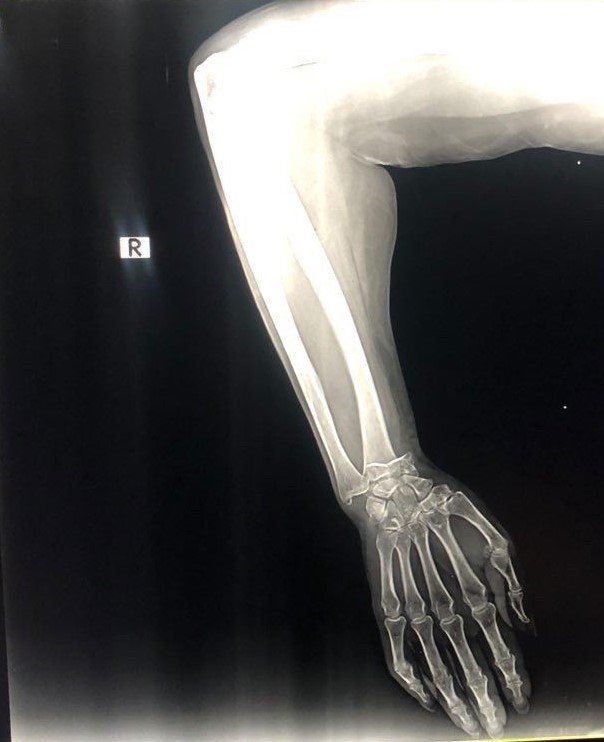

Olay, 4 Ağustos Cuma günü Kemer ilçesi Aslan Bucak Mahallesi Cuma pazarında yaşandı. Savaştan kaçıp Antalya'ya yerleşen Olena Buletsa (61), burada Şeyhmus Doğan ile yakın bir tarihte evlenen kızı Kateryna Buletsa'la (32) pazar alışverişine çıktı. Kızıyla birlikte yürüdüğü sırada dengesini kaybedip yere düşen Olena Buletsa'nın bileği kırıldı. Çevredekilerin durumu 112 Acil Çağrı Merkezine bildirmesi üzerine Buletsa ambulansla Kemer Özel Yaşam Hastanesine götürüldü. Burada iddiaya göre, sadece röntgen ve alçıya bin 680 dolar (günün kuruyla 44 bin 555 TL) fatura kesildi. Buletsa ve kızı bu parayı ödeyip evlerine döndü. Faturayı gören damadı Şeyhmus Doğan hastaneye gidip faturaya hastane çalışanları ve yetkililerine tepki gösterip itiraz etti. Olaydan bir gün sonrası ise 850 dolar Kateryna Buletsa'nın hesabına geri yatırıldı.

"Bir röntgen çekildi, ardından cerrah kolu ayarladı ve bir alçı uyguladı. Sonuçta doktor alçının geçici olduğunu ve ameliyat gerektiğini söyledi. Bize bin 650 dolarlık bir fatura verdiler. Operasyonun miktarını belirtmediler. Bütün bunların Ukrayna'da çok daha ucuz olacağını düşünüyorum. Alçı yaklaşık 30 dolara mal olacak ve ameliyat yaklaşık 800 dolara mal olacak. Ukrayna'da bir savaş var. Oradan kaçıyoruz. Yardım istedik. Ve bu hastanenin hizmetleri için çok büyük parayı ödedik. Ukrayna'da alçı fiyatı yaklaşık 30 dolar. Kısacası, acil bakım, enjeksiyon, röntgen ve geçici alçı için bin 650 dolar aldılar. Annem Ukrayna'ya gidip muayene olacak" diye konuştu.